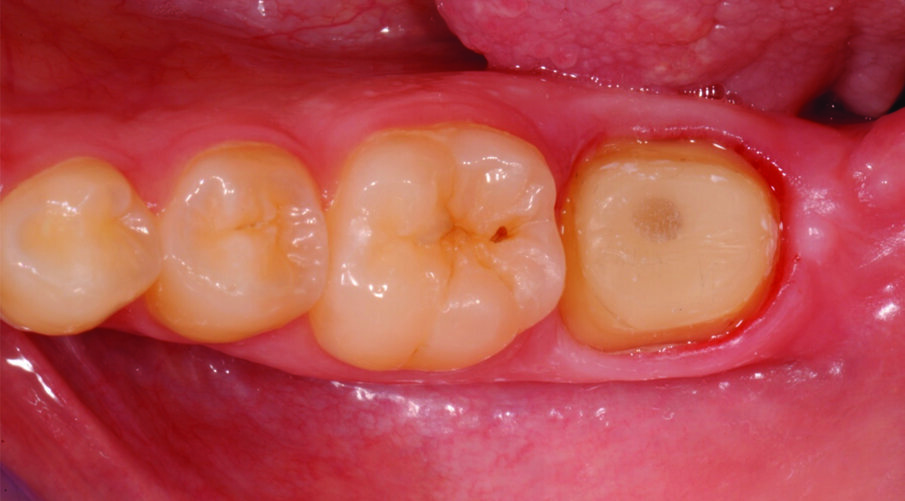

Fig. 2: Tooth preparation after post placement and core build up with a low shrink composite. Retraction in place. Impression with polyether impression materials.